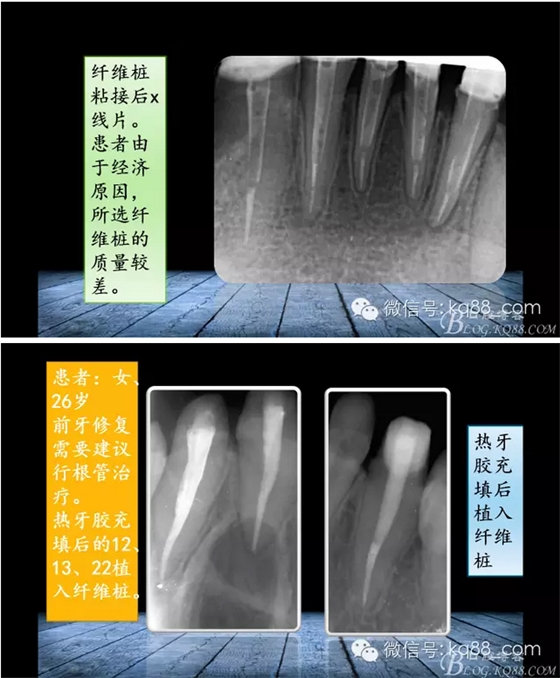

QQ圖片20150817140633.png

QQ圖片20150817140707.png